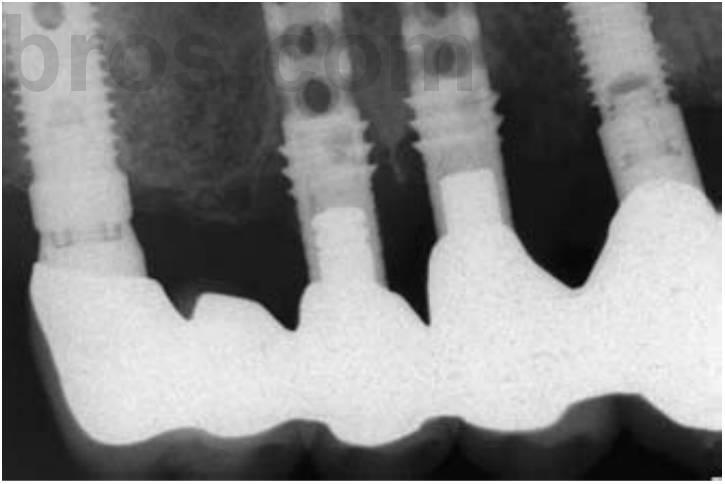

El estrés global sobre todo el sistema del implante puede reducirse aumentando el área sobre la que está aplicada la fuerza. El método más efectivo para aumentar el área de la superficie de soporte del implante consiste en aumentar el número de implantes de soporte de la prótesis (fig. 4-32). Por ejemplo, estudios previos de Bidez y Misch han demostrado que la fuerza distribuida sobre tres pilares da como resultado un estrés menos localizado en la cresta del hueso que con dos pilares. Este estudio se aplica únicamente a los implantes que están ferulizados conjuntamente. De ahí que, cuando las fuerzas están aumentadas, debería reducirse el número de pónticos y aumentar el de pilares de implantes, en comparación con la planificación de tratamiento para un paciente ideal con factores de fuerza mínimos.

La retención de la prótesis también se ve mejorada con un mayor número de pilares ferulizados. Este enfoque disminuye también la incidencia de las restauraciones no retenidas. Los implantes ferulizados disminuyen también las fracturas de la porcelana. Se reduce la cantidad global de estrés sobre el sistema, y los rebordes marginales de las coronas de los implantes son soportadas por las conexiones de las coronas ferulizadas, dando como resultado más fuerzas compresivas que las cargas intermitentes sobre la porcelana.